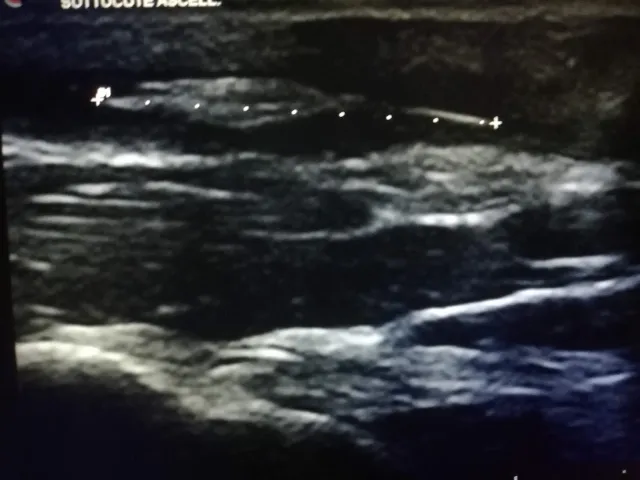

Diagnostica avanzata

Ecografie, radiologie digitali ed esami di laboratorio